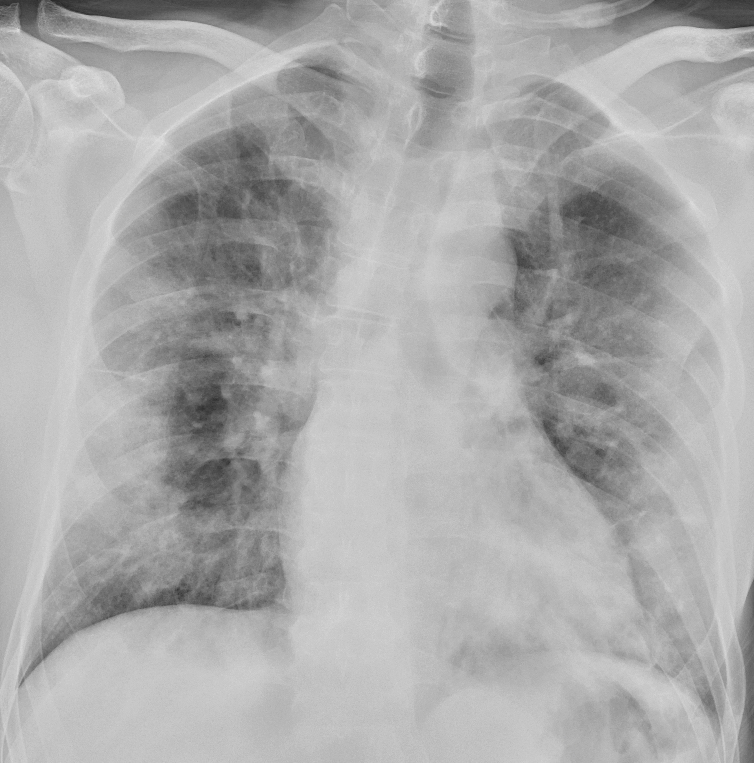

I et materiale fra Hongkong hadde 69 % funn på røntgen thorax før behandling (baseline), men 9 % hadde funn på røntgen thorax før positiv PCR (14). Sensitiviteten for røntgen thorax var 69 % og for PCR 91 %. Vanligste røntgenfunn var bilateral konsolidering og mattglassfortetninger med perifer og kaudal distribusjon. Forandringene var mest uttalt 10–12 dager etter symptomdebut. Figur 1 og figur 2 viser typiske funn på røntgen thorax ved covid-19.

Hos inneliggende pasienter kan et sengebilde i tidlig stadium være nyttig som sammenligningsgrunnlag for tolking av bilder tatt senere. Hos pasienter med alvorlig sykdom vil det være indisert med sengebilder for kontroll av medisinskteknisk utstyr (figur 3), men det er ikke indisert med daglig, rutinemessig røntgen thorax hos stabile pasienter. I forløpet av sykdommen vil det være indisert med sengebilde ved mistanke om komplikasjoner og ved oppfølging og monitorering av sykdomsprogresjon.